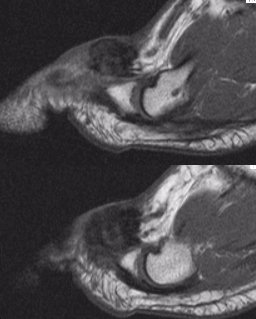

Case 5 (Menu)

gctts1.jpg (17017 bytes)gctts2.jpg (16162 bytes)